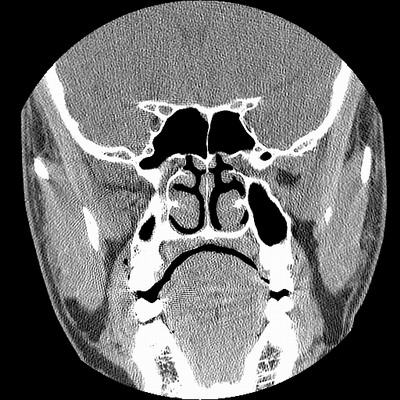

男,38岁,鼻塞、头痛2个月,要求鼻窦ct检查。

右侧上颌窦、蝶窦、筛窦、额窦及左侧上颌窦慢性炎症。

右侧鼻中隔左偏,右侧上颌窦、筛窦、额窦慢性炎性病变。右侧上颌窦开口粘膜增厚。

1)副鼻窦炎。2)右侧中鼻道及总鼻道粘膜息肉样变。3)双侧中下鼻甲肥大。4)鼻中隔轻度左突偏曲。